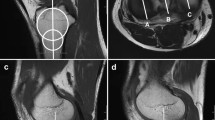

The literature suggested that separate assessment of the PTS was not reliably possible on lateral radiographs, the reliable and reproducible methods conducted on MRI or computed tomography (CT) images were recommended to measure the PTS [12]. It varies in the literature regarding the definition of the lateral tibial axis on MRI [13, 14], we conducted the method described by Hudek et al. [15], which was reported to be the most repeatable and reliable method to measure sagittal tibial slopes on MRI [13]: a T1-weighted mid-sagittal cut was selected with the appearance of PCL-tibial insertion point, the tibial axis was defined as the line through both center of circles drawing on the sagittal image, and tibial axis was used to measure the medial and lateral PTS (Fig. 1) and MS (Fig. 2) on the other two sagittal images (the mid-medial tibial plateau cut and the mid-lateral tibial plateau cut), respectively.

Lateral and medial PTS. A sagittal MRI image shows the tibial attachment of the PCL and the intercondylar eminence. C1: circle 1 has to touch the anterior, posterior, and cranial tibial cortex bone C2: circle 2 has to touch the anterior and posterior cortex border. The longitudinal axis (LA) of the proximal tibia was defined by a line that connected the centers of these two circles. B sagittal MRI image shows the center of the medial tibial plateau, the LA is superimposed on the selected image. Line a: the line tangent to the medial plateau. Line b: the line perpendicular to LA. The angle between line a and line b is defined as medial PTS. C sagittal MRI image shows the center of the lateral tibial plateau. Line c: the line tangent to the lateral plateau. Line d: the line perpendicular to LA. The angle between line c and line d is defined as lateral PTS